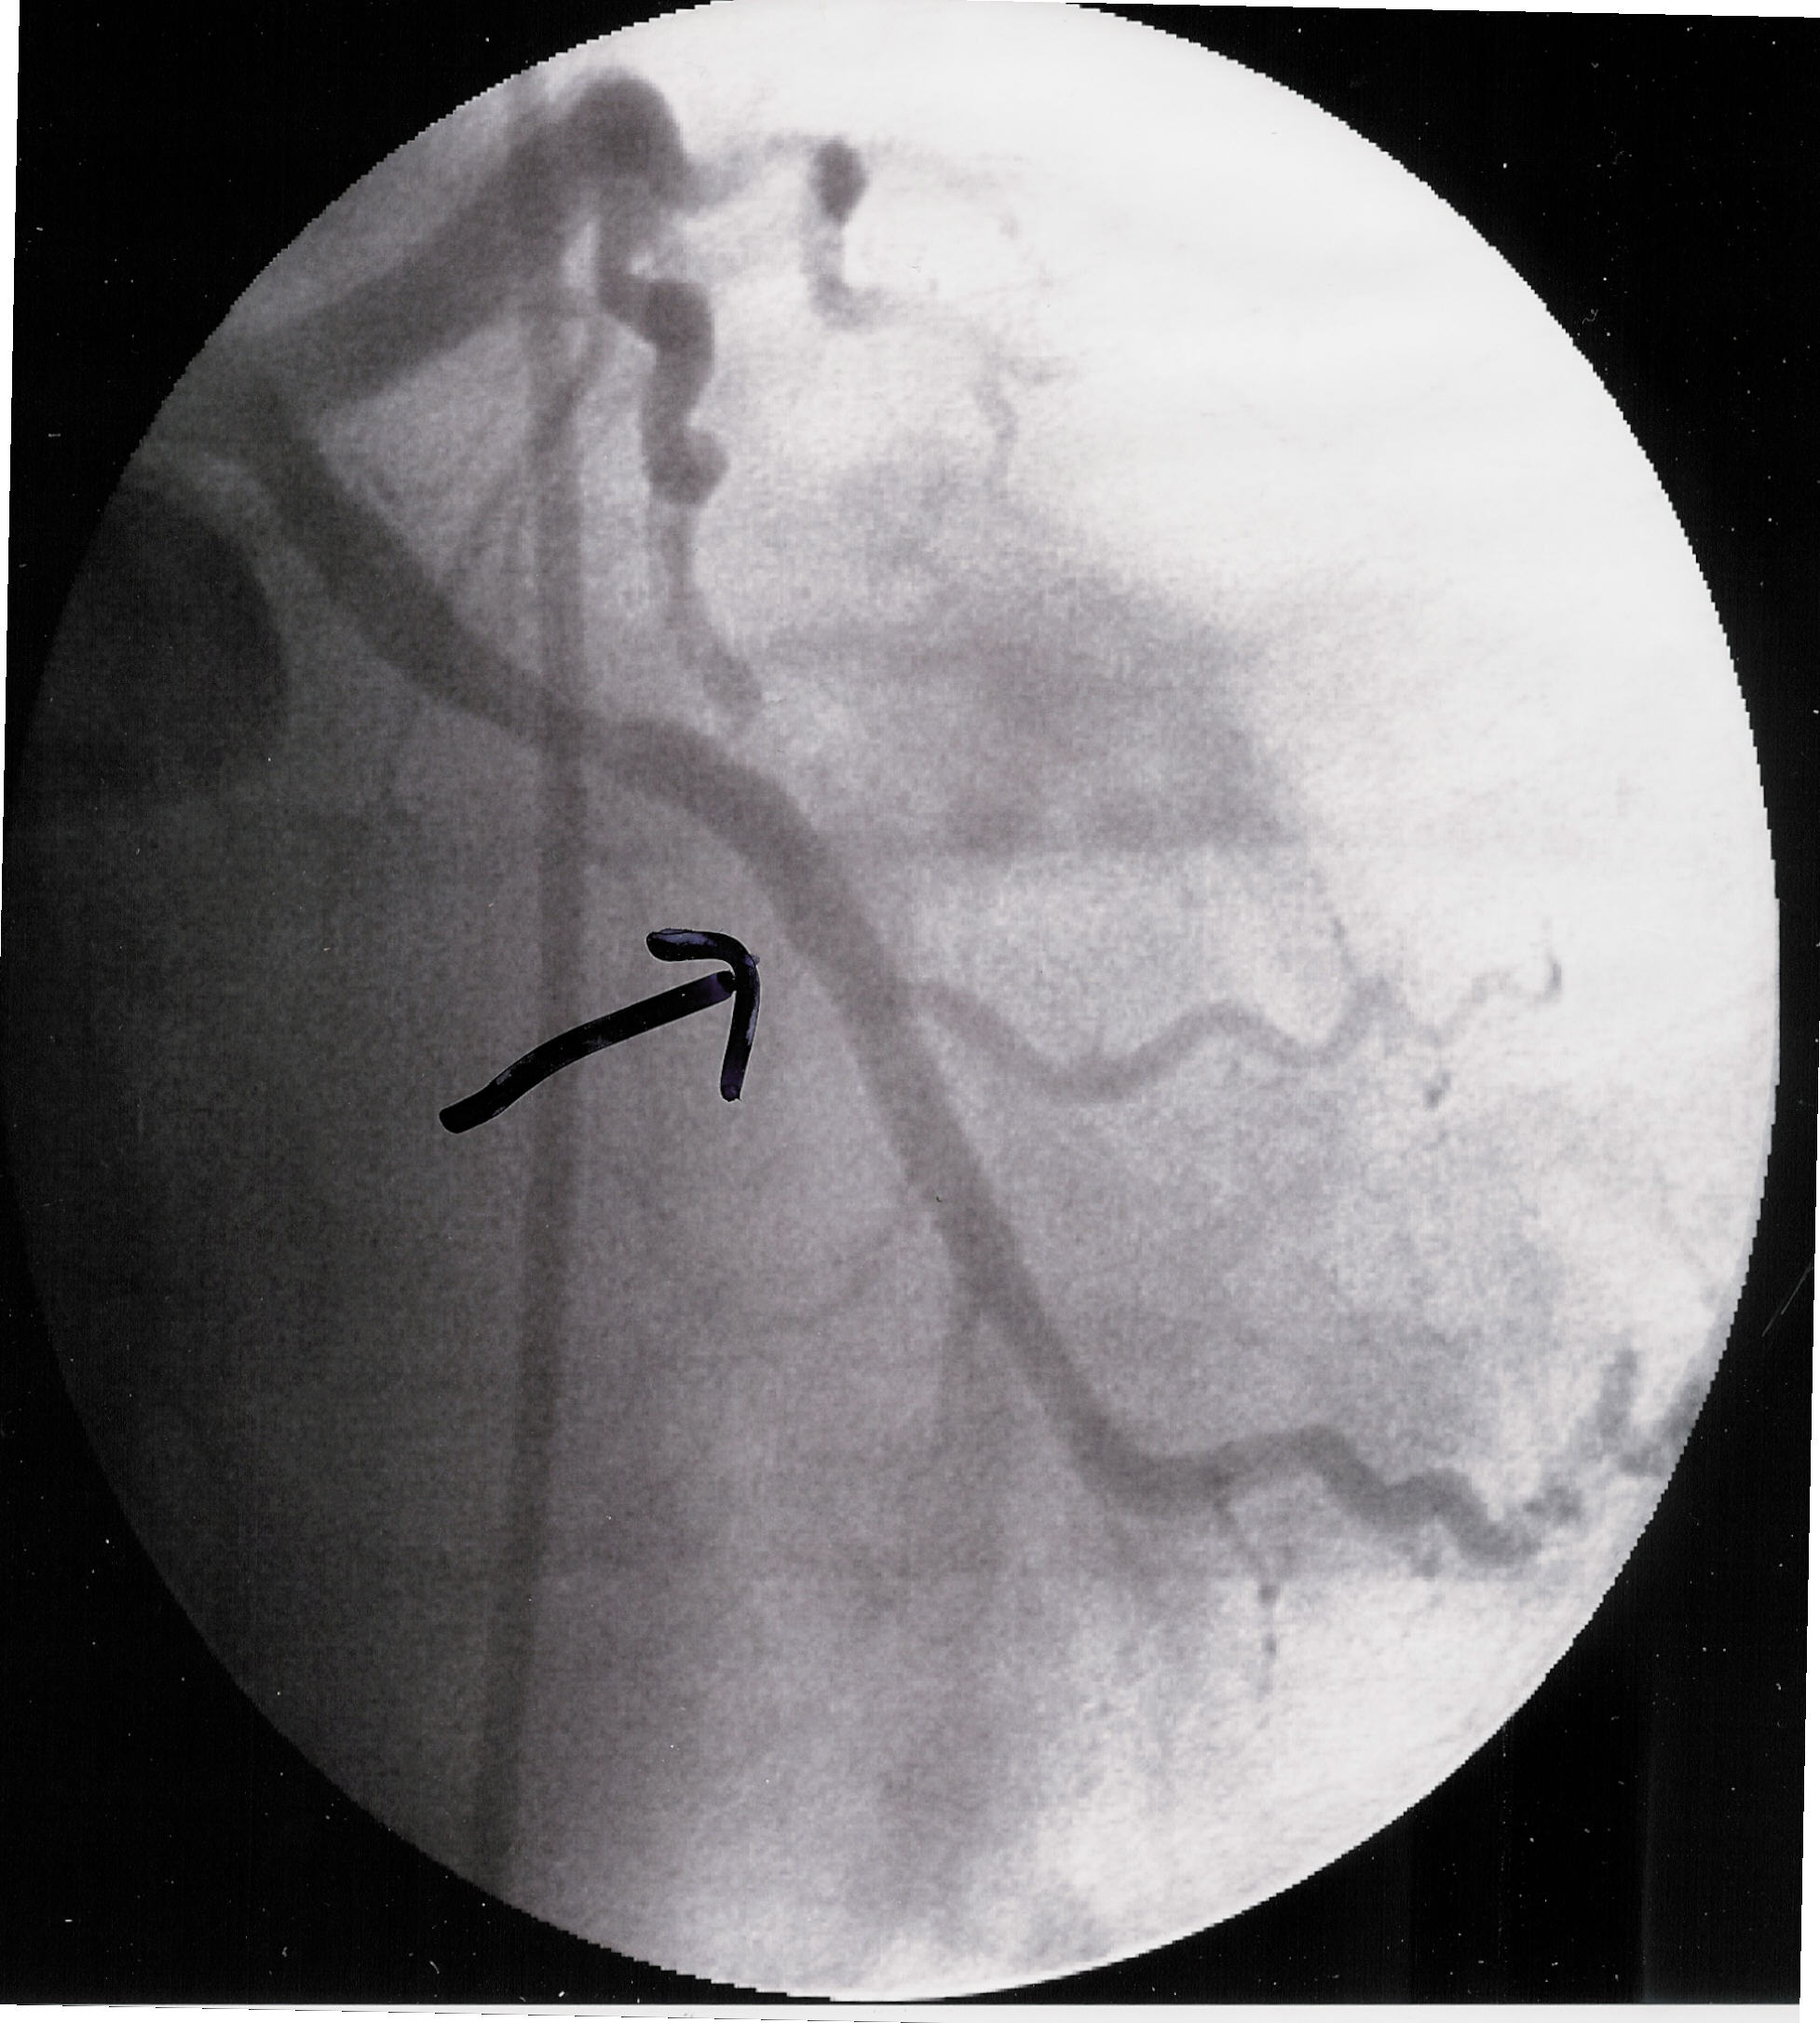

Friday Morning at 11:30 they took me into the operating

theater and started there stuff. and here is the result below. It appears to

be the oxygen veins that supply oxygen to the heart. The doc told me I would

After